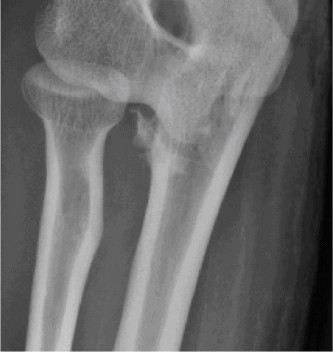

The patient undergoes resection arthroplasty with antibiotic cement spacer and a 6-week course of IV antibiotics. He returns to clinic 4 months later with improved pain, CRP <3, however, on examination he has a positive belly press sign and increased external rotation compared with the contralateral shoulder. Imaging is shown in Figure 2–57.

Figure 2–57

The correct answer is (D). The patient has completed his course of antibiotics and his spacer and is now an appropriate candidate for explanation of the cement spacer with revision shoulder arthroplasty, therefore Choices A and C are incorrect. The patient’s clinical examination findings point to rotator cuff tear (specifically subscapularis) which has occurred in the interval between his obtaining his initial total shoulder arthroplasty and his current examination. Therefore, total shoulder arthroplasty (Choice B) is contraindicated, and the patient should have a reverse total shoulder arthroplasty. Objectives: Did you learn...? Recognize the clinical presentation of a patient with infection after total shoulder arthroplasty?